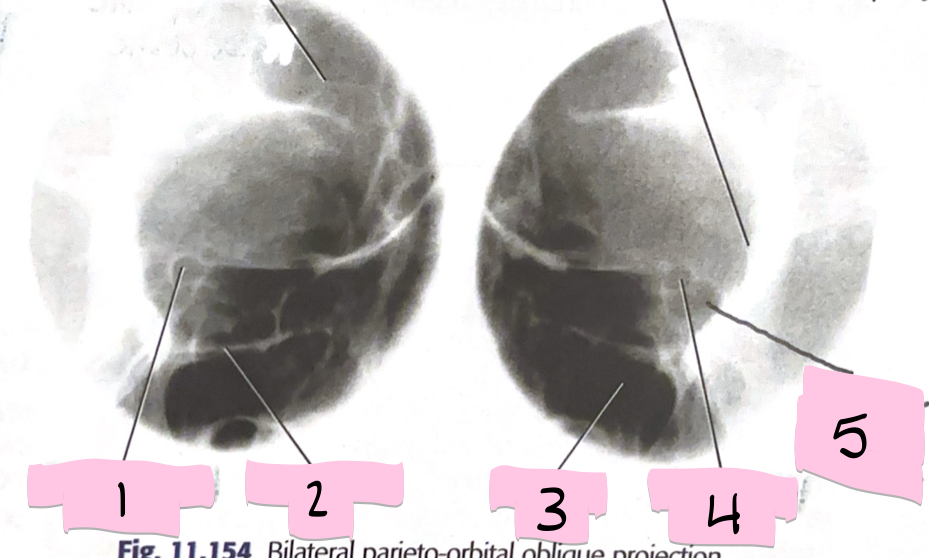

What is 1 pointing to?

Optical foramen and canal

What is 2 pointing to?

Inferior orbital rim

What is 3 pointing to?

Maxillary sinus

What is 4 pointing to?

Optic foramen and canal

What is 5 pointing to?

Superior orbital fissure